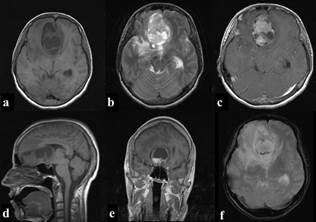

A Computerized-Tomography (CT) scan was performed revealing the presence of an anterior fossa tumefaction, without any accompanying malformations. Magnetic-ResonanceImaging (MRI) confirmed the presence of a heterogeneous contrast-enhancing neoplasm consisted of an admixture of solid and cystic formations (Figure 1).

Figure 1 Brain MRI: Axial (a) and sagittal (d) T1 weighted slices presenting a frontal fossa neoplasm of heterogenous intensity, including solid areas and a significant number of cystic degenerative formations. A subfalcine herniation, associated with the volume effect can also be detected. Axial (b) T2 weighted slice confirming the aforementioned and highlighting the presence of significant perilesional edema. Axial (c) and coronal (e) T1 weighted, post-gadolinium images showing heterogeneous enhancement. A slight circumferential blooming is also registered in axial (f) T2 weighted gradient echo.